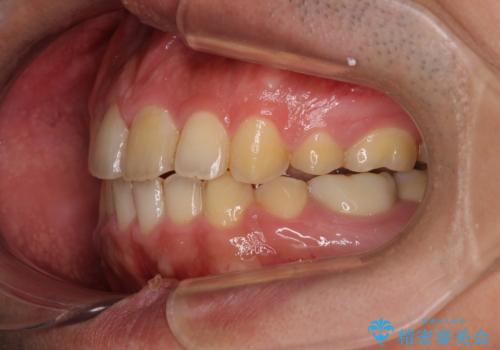

後戻りでデコボコの前歯 インビザライン矯正治療

- 高校時代に行った抜歯矯正が後戻りをしたとのことで来院された患者様です。

再矯正であることから、目立ちにくい装置を希望されたため、インビザラインにて矯正治療を行うこととしました。

下顎骨が左側に変位しているため、正中が合わないことは予想できましたが、歯列が整った後も咬み合わせが安定せず、咬み合わせを落ち着かせるために1年以上の期間を要しました。